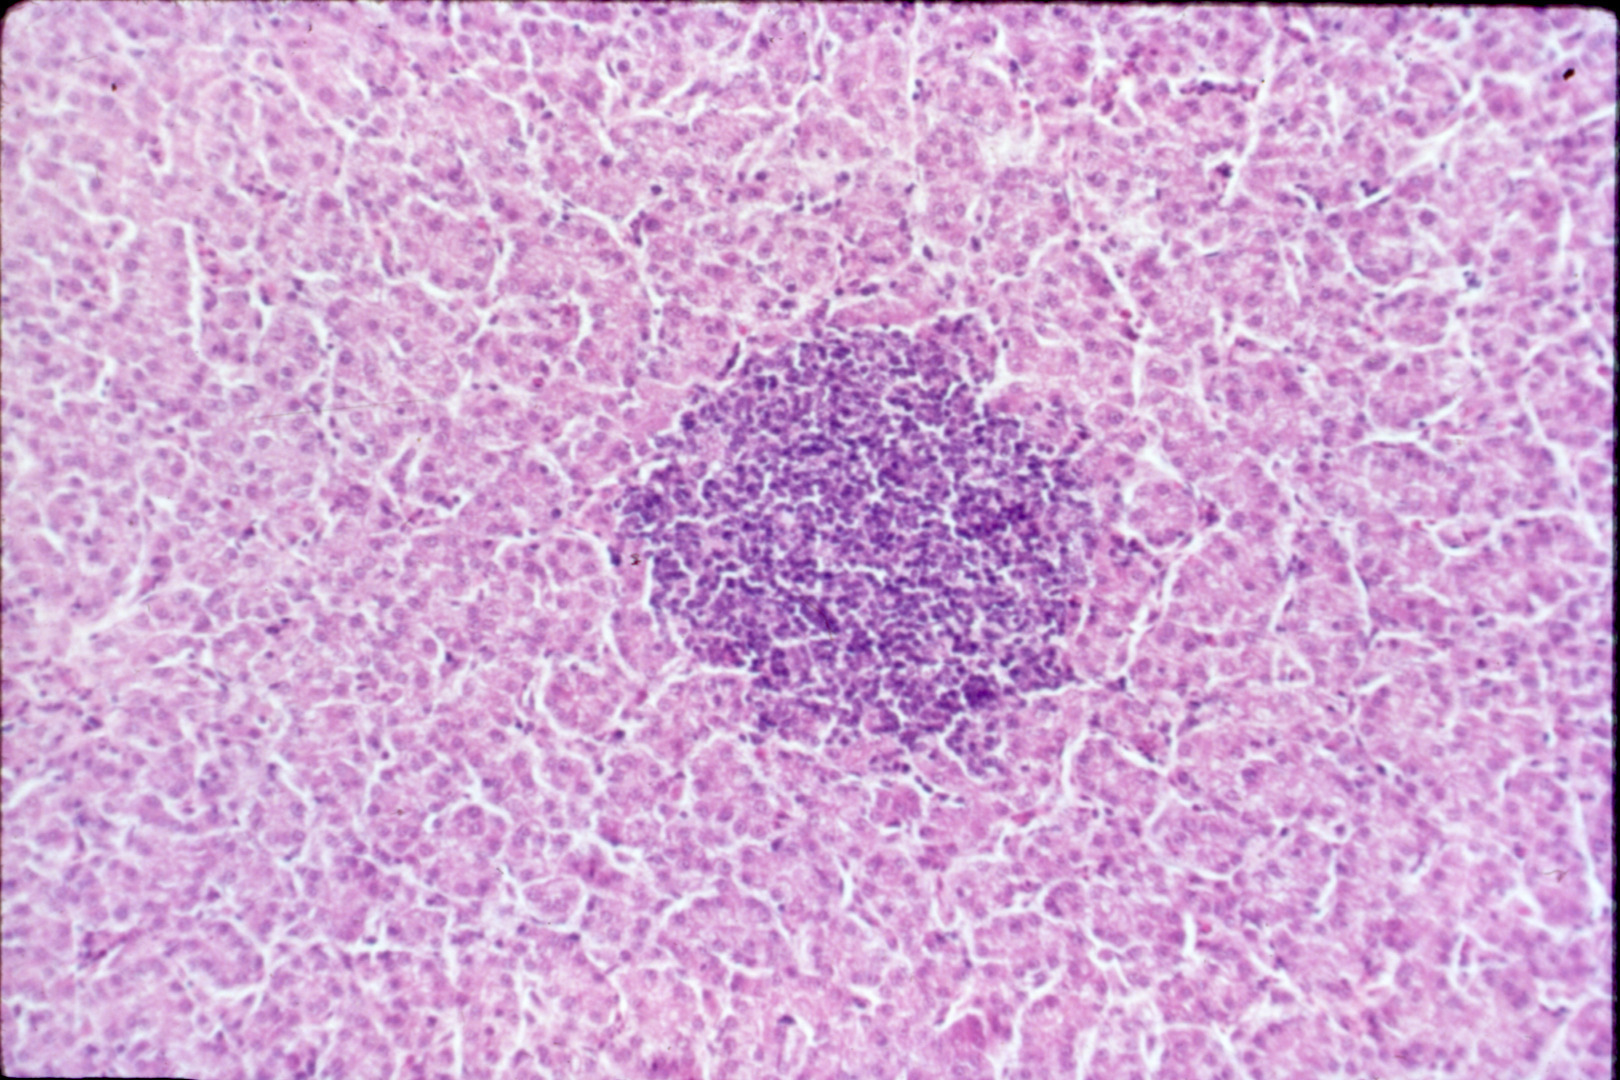

Avian encephalomyelitis (slide study set no. 5)

Avian encephalomyelitis Avian medicine Chickens--Diseases Turkeys--Diseases Pheasants--Diseases

Slide Study Set #5, Avian Encephalomyelitis, 2 sets (includes 32 color slides), 1974